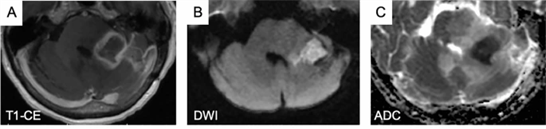

4.2. Cộng hưởng từ khuếch tán (DWI- Diffusion weighted imaging)

Hình 4: A. Ảnh T1 có tiêm thuốc đối quang từ cho thấy sự tăng tín hiệu dạng vòng. B. Hình ảnh Diffusion và C. Bản đồ ADC cho thấy sự hạn chế khuếch tán bên trong tổn thương tăng tín hiệu dạng vòng.

DWI cho phép đo độ khuếch tán như một hệ số khuếch tán biểu kiến (ADC), có thể được sử dụng để giúp phân biệt hoại tử não do bức xạ với sự tiến triển của khối u. Sự tăng sinh tế bào khối u nhanh chóng làm tăng mật độ quần thể tế bào và màng tế bào bán thấm trong một voxel nhất định, dẫn đến giảm tuyến tính độ khuếch tán nước và do đó làm giảm giá trị ADC được đo. Hoại tử, phù nề và bất kỳ quá trình bệnh lý nào cũng phá vỡ màng bán thấm làm giảm mật độ tế bào và tăng giá trị ADC theo tỷ lệ. Chụp ảnh tensor khuếch tán (DTI) là một biến thể của DWI, thu thập thông tin bổ sung liên quan đến hướng chuyển động của nước bên trong các voxel dưới dạng bất đối xứng phân đoạn (FA- Fractional anisotropy). Hoại tử gây mất cấu trúc tế bào và các sợi bình thường, từ đó phá vỡ sự khuếch tán nước, tạo ra các giá trị FA thấp. Điều thú vị là, các giá trị FA thấp cũng có thể gặp trong một khối u đang phát triển, do sự gián đoạn trong nhu mô xung quanh. Có dữ liệu hạn chế về lợi ích của FA trong việc phân biệt hoại tử não do bức xạ với sự tiến triển của khối u ở các khối u não nguyên phát và di căn.